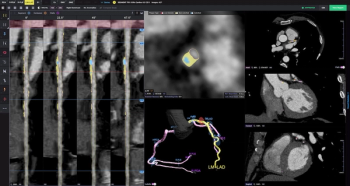

Al-powered quantitative assessment of coronary CT angiography (CCTA) revealed that non-calcified plaque volume was over 3.5 times higher in patients who had major adverse cardiovascular events, according to multicenter research presented at the Transcatheter Cardiovascular Therapeutics (TCT) conference.

Through analysis of coronary computed tomography angiography (CCTA) images, the PlaqueIQ software provides quantification and classification of atherosclerosis, a common cause of myocardial infarction (MI) and ischemic stroke.